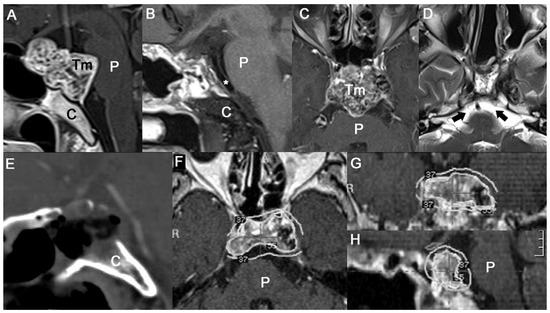

2.2. Surgical Strategy

2.3. Endonasal Transclival Approach